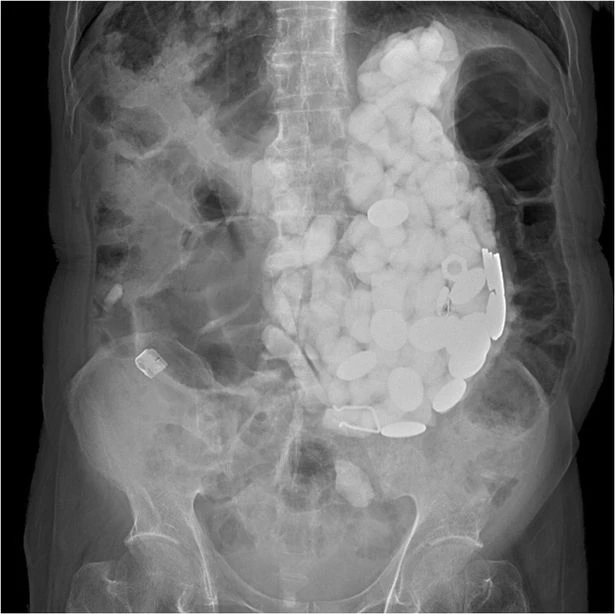

Các bác sĩ tiến hành một số xét nghiệm để tìm nguyên nhân dẫn đến triệu chứng. Bác sĩ nhận thấy rằng họ có thể cảm thấy “thứ gì đó như những viên đá nhỏ” khi ấn vào bụng bệnh nhân, theo báo Mirror.

Bác sĩ nhận thấy “có gì đó giống như những viên đá nhỏ”.                             Ảnh:  AMERICAN JOURNAL OF MEDICAL CASE REPORTS